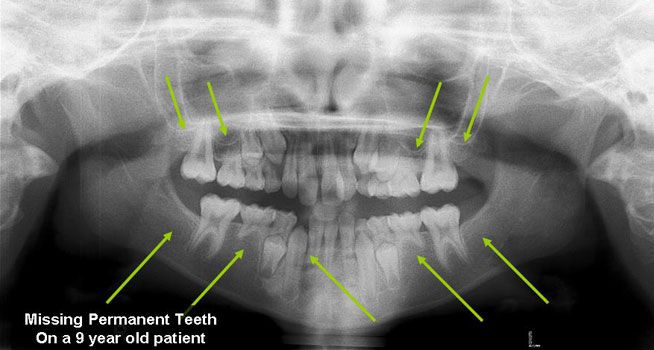

Missing Permanent Teeth

Hypodontia (the common dental term) describes a situation when fewer than 6 permanent teeth are missing, the term Oligodontia is used when more than 6 permanent teeth are missing (they were never formed). The most common missing teeth are the third molars (otherwise known as the Wisdom Teeth), followed by the premolars and the lateral incisors. Although it is not uncommon to have one missing tooth, patients with multiple missing teeth generally have a strong genetic component and it has been linked to conditions such as Ectodermal Dysplasia and several syndromes. Because early recognition aids in proper treatment, your dentist will refer you to specialists (orthodontist, oral surgeons, etc) that will determine which options suit you best to replace the missing teeth.